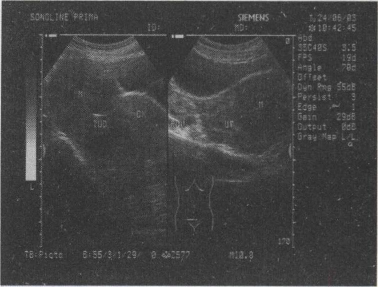

48.女,33岁,因月经不调就诊,超声声像如图,最可能的诊断为()